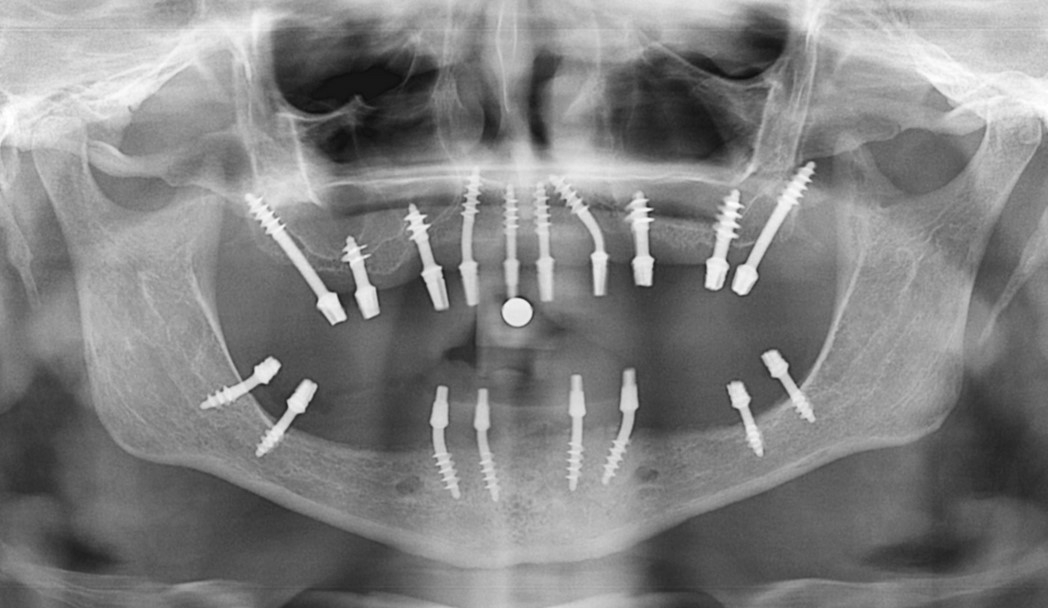

Исследование на рентгене после имплантации зубов

Раздел: Снимки-откровения